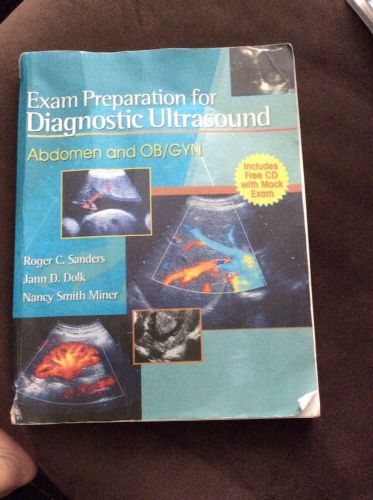

Exam Prep For Ultrasound, Abdomen Sonography And Ob/Gyn Sonography